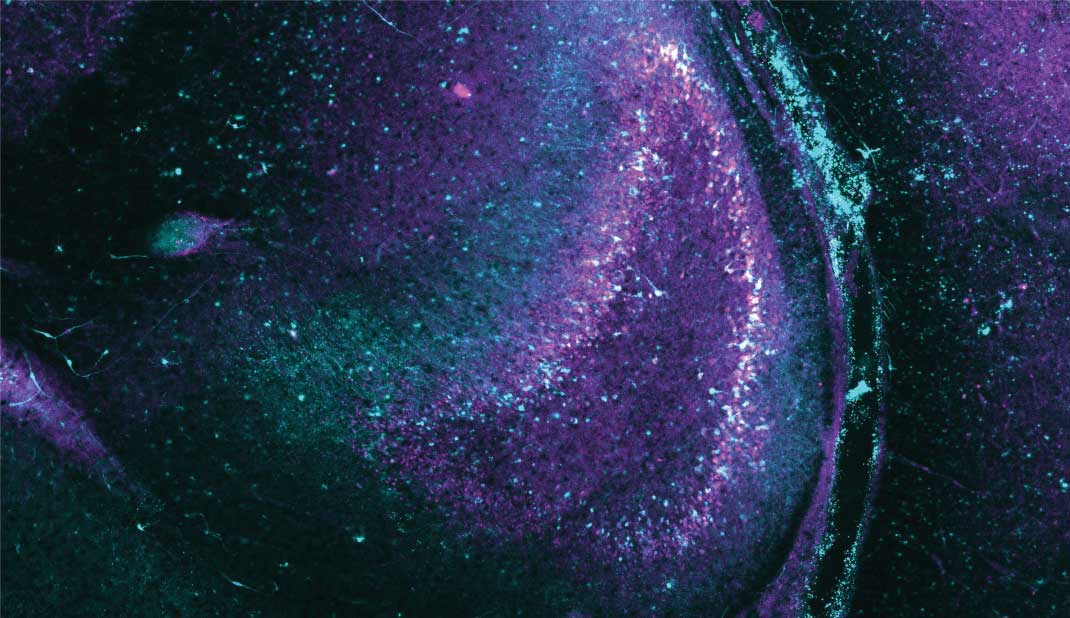

These images show how seizure-like activity can be subdued by pulses of light in a slice of living brain tissue containing light-sensitive proteins.

The pink and yellow reflect seizure-like activity before the light is turned on.

When the cells are illuminated, the abnormal activity dissipates.

When the light is turned off, abnormal activity starts up again.